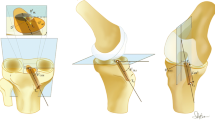

These measurements were taken in the CHK first, fixing the clusters by Steinmann pins. The clusters were then moved to the ADK and fixed by minimally invasive unicortical Schanz screws. The manual laxity tests were repeated and collected by the system before surgery, after isolated IAR and finally after the additional minimally invasive ALR. For IAR, the autologous semitendinosus tendon was taken and prepared for a short four-bundle single-tunnel montage, whose extremity graft was fixed 15 mm inside the tibial bone tunnel. The femoral tunnel was drilled by the anteromedial portal, and femoral fixation was secured with a transverse cross-pin system inserted close to the femoral entry tunnel (Fig. 1a). The graft was pre-tensioned for 10 min at 10 Newton and subsequently fixed at 30° of knee flexion with manual tensioning enabling the knee to be lifted from the operating table. The ALR [24] involved folding the autologous gracilis tendon and making a free 11-cm-long graft, inserted from a femoral position 1 cm proximal and posterior to the lateral epicondyle to a tibial margin position against the posterior aspect of the Gerdy’s tubercle. Interference screws inside bone tunnels were used for femoral and tibial fixation of the graft. Drilling the tunnels, inserting the graft and fixing it with interference screws were performed through two 1.5-cm-long incisions. Between them, graft application was completed by blunt dissection under the fascia lata through the distal incision with crocodile forceps (Fig. 1b). The graft was secured with 90° of knee flexion and 0° of internal–external rotation.

The extent to which joint laxity after surgery is compared with that at the CHK varied by test, flexion angle and compartment (Table 2). In the anteroposterior drawer test, IAR alone restored significantly physiological laxity, in both rotation and translation at both compartments, but at 20° flexion only; at 90°, this was true only for the translation in the lateral compartment. This reduced effect in the medial compartment, although compensated after ALR, suggests that additional anatomical structures might have been damaged with injury or might have progressively deteriorated over time between injury and surgery. The associated residual varus–valgus laxity can be accounted for by possible lesions to the medial part of the knee. The posteromedial capsule must be in tension and resist valgus, posterior tibial translation and internal rotation but only with the knee extended [36, 63]. In our series of isolated ACL injuries, none of the 32 patients had a history of more than grade I medial collateral ligament lesion or an increase in varus–valgus laxity upon clinical examination. Therefore, more attention should be devoted to these anatomical structures since minor injuries at initial trauma or progressive distension before surgery can both lead to non-physiological laxity [46]. It has been suggested that peripheral anatomical structures are the primary restraints to tibial rotation [1, 43]. Peripheral anterolateral lesions were reported intra-operatively in 93 % of ACL reconstructions [55] and are commonly observed by MRI [8]. The anterolateral ligament has been described as an additional potential capsular rotational stabilizer [11]. The unsuccessful restoration of medial compartment restraint may also explain the degenerative changes which occur mostly at the medial compartment [37] even after a successful ACL reconstruction with negative pivot-shift test and normal anteroposterior translation [44]. In this respect, a minimal invasive acute medial collateral ligament stabilization has been proposed in case of partial ACL deficiency [15]. Interestingly, in our drawer test at 20°, translation in the medial compartment significantly deteriorated from IAR to ALR conditions: we hypothesize that the pivot-shift manoeuvre performed immediately after IAR resulted in a mild distension of the graft, by tensioning the implants inside the bone bed. The anterolateral reinforcement might also contribute to overloading the medial compartment by a lateral displacement of the knee rotation centre. ALR corrected significantly the varus–valgus laxity with respect to ADK, but that was not enough to return this to the physiological condition. Because it was unfeasible to separate the amount of varus and valgus laxity, it was not possible to assess whether ALR contributed to correct the latter due to lateral peripheral lesions or the former due to medial peripheral lesions. However, this test was performed in full extension, where a healthy lateral collateral ligament is tightened to prevent valgus laxity.

By looking at the pivot-shift test, IAR was able to return the knee close to physiological laxities, IAR + ALR to even a slightly better extent, although neither were significantly different from CHK. IAR was in fact expected not to reproduce fully the natural rotational control, which might be better achieved by a more “anatomic” single- or double-bundle reconstructions [22, 33]. Possible anterolateral peripheral lesions might have occurred as well in our patients at the time of injury or between injury and surgery, as documented in the literature [1, 8, 43, 55]; a relevant adjunction of an anterolateral reinforcement during ACL reconstruction has been reported [14, 40, 57]. Indeed, in our study, the IAR corrected the coupled rotation during pivot-shift test.

Laxity at the lateral compartment in all relevant tests was largely restricted. This is apparently the main drawback of the ALR, partially because this implies a lateral displacement of the rotation centre, subsequently reducing overall joint mobility, while increasing it in the medial compartment. These effects combined with a modification of the translation–rotation balance may lead to long-term degenerative changes [2, 18]. A non-isometric graft placement can be considered to address this, and though the present femoral graft insertion is the most appropriate to control tibial internal rotation [31], other authors have proposed a more posterior tibial fixation back to the posterior aspect of the Gerdy’s tubercle to enhance isometry [10, 35]. Future contribution for the best possible placement of ALR can take advantage of the recent anatomical descriptions of the anterolateral ligament [9, 11, 60]. Viscoelasticity of the graft must also be considered: the different properties with respect to natural tissue likely result in inadequate mechanical response to dynamic loading [51, 59].